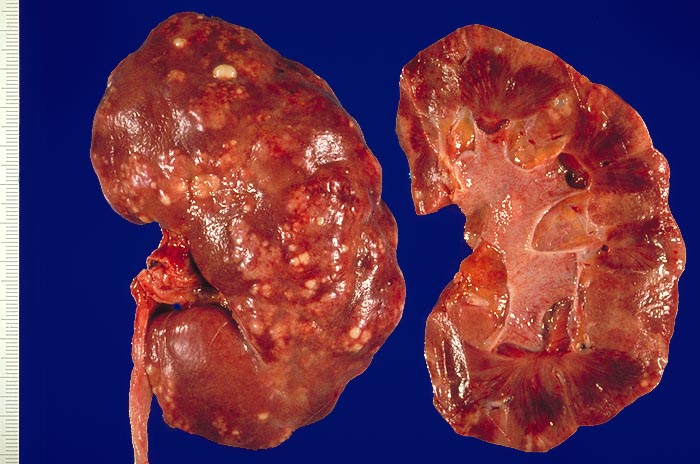

Schwerste akute Pyelonephritis. An der Nierenoberfläche erkennt man zahllose gelbe, leicht erhabene Herde, die von einem zarten roten Randsaum umgeben sind. Daneben bestehen kleinere Narbenfelder mit Einziehung der Niererinde. Auf der Schnittfläche sieht man Eiterstrassen, welche das Parenchym von der Papille bis zur Rinde durchziehen. Rötung der Nierenbeckenschleimhaut (Pyelitis).